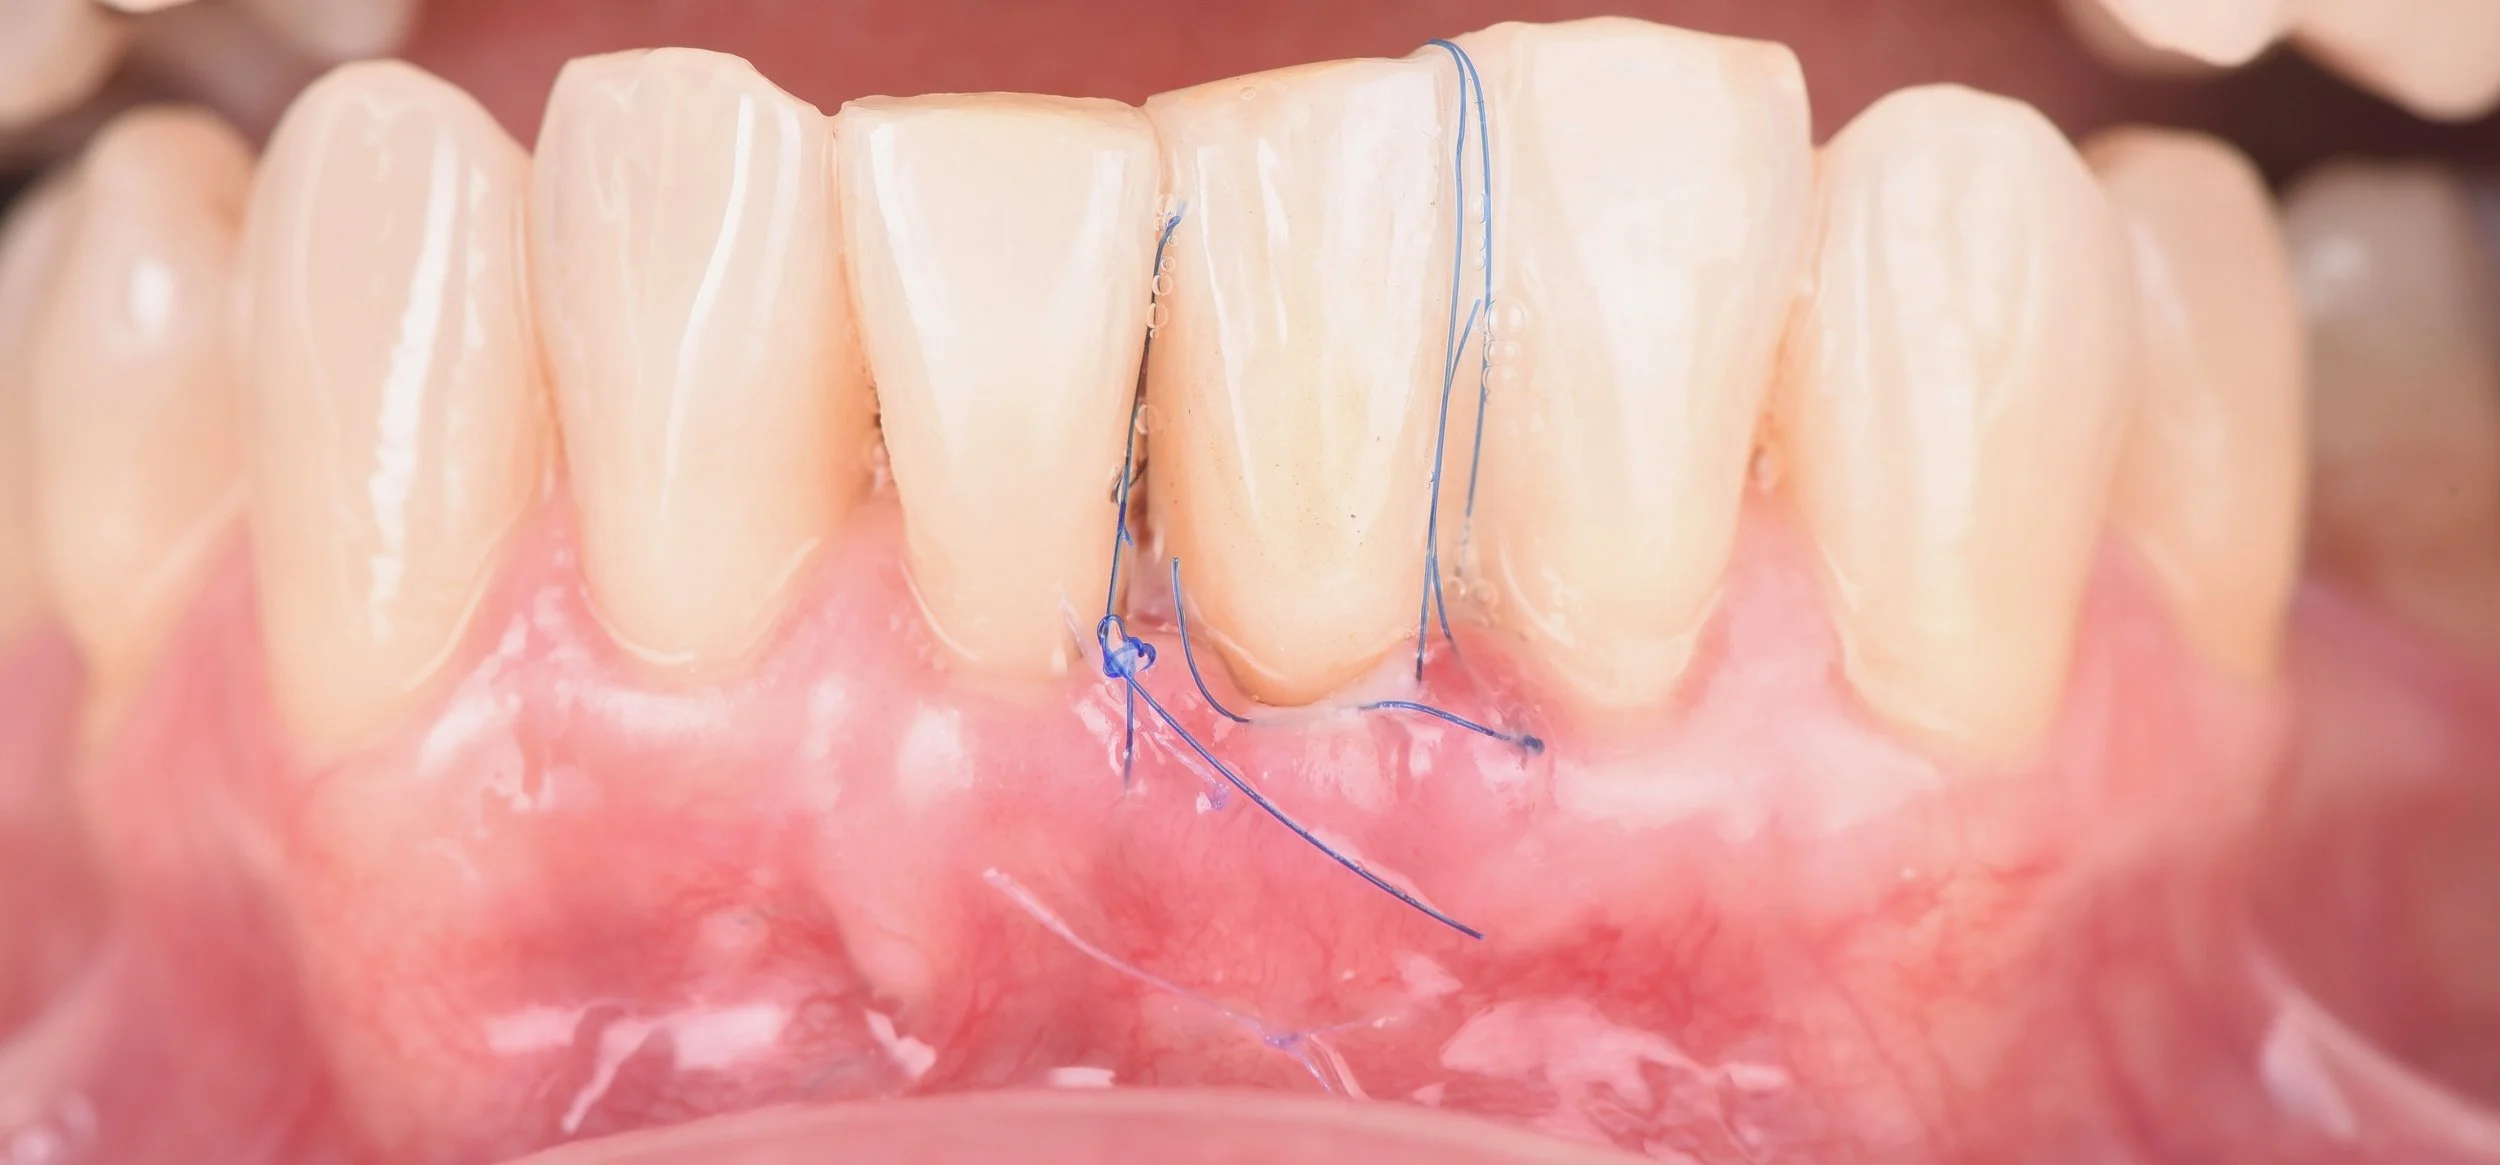

• Le principe de la tunnelisation

• Simplification des procédures de tunnelisation = optimisons le décollement

• Les sutures = comment choisir son matériel et quels points réaliser ?

• Greffe de gencive par tunnelisation au maxillaire

• Travaux pratiques : Réalisation d’une greffe par tunnelisation sur mouton